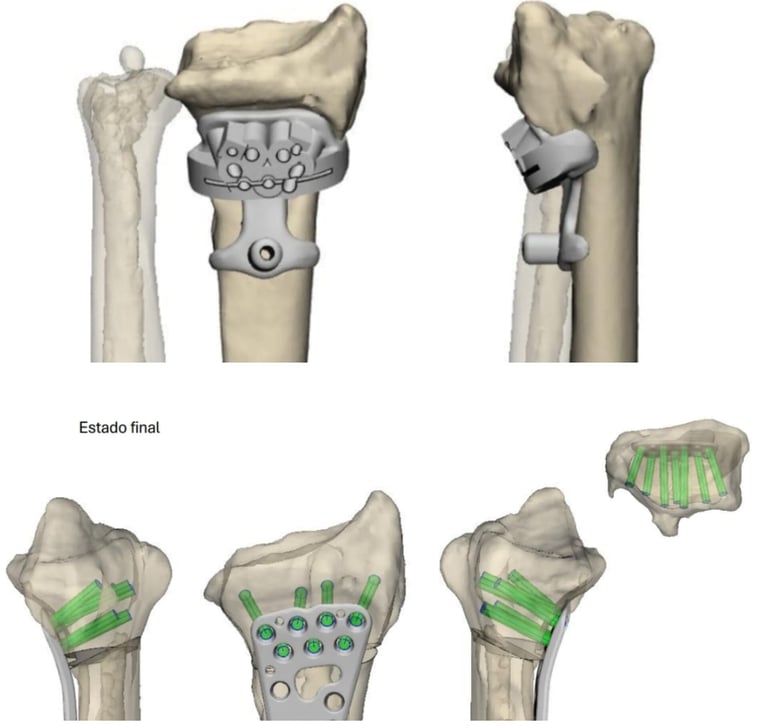

Planificación con impresión 3D

Impacto de los avances en pacientes y profesionales médicos.